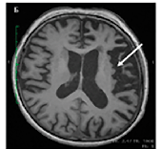

Атрофические изменения в нижней лобной извилине (зона Брока) и островковой коры левого полушария |

|

лППА |

Трудности актуализации – подбора и называния слов. Нарушение повторной речи. Сужение объема слухоречевой памяти |

Атрофические изменения в височной и теменной долях доминантного полушария |